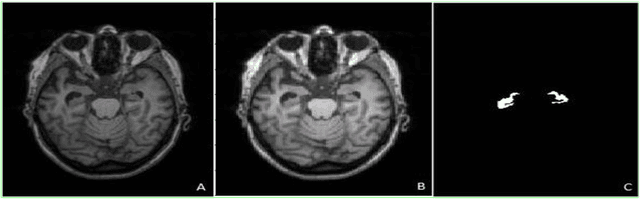

Abstract:Background: Alzheimers disease is a progressive neurodegenerative disorder and the main cause of dementia in aging. Hippocampus is prone to changes in the early stages of Alzheimers disease. Detection and observation of the hippocampus changes using magnetic resonance imaging (MRI) before the onset of Alzheimers disease leads to the faster preventive and therapeutic measures. Objective: The aim of this study was the segmentation of the hippocampus in magnetic resonance (MR) images of Alzheimers patients using deep machine learning method. Methods: U-Net architecture of convolutional neural network was proposed to segment the hippocampus in the real MRI data. The MR images of the 100 and 35 patients available in Alzheimers disease Neuroimaging Initiative (ADNI) dataset, was used for the train and test of the model, respectively. The performance of the proposed method was compared with manual segmentation by measuring the similarity metrics. Results: The desired segmentation achieved after 10 iterations. A Dice similarity coefficient (DSC) = 92.3%, sensitivity = 96.5%, positive predicted value (PPV) = 90.4%, and Intersection over Union (IoU) value for the train 92.94 and test 92.93 sets were obtained which are acceptable. Conclusion: The proposed approach is promising and can be extended in the prognosis of Alzheimers disease by the prediction of the hippocampus volume changes in the early stage of the disease.